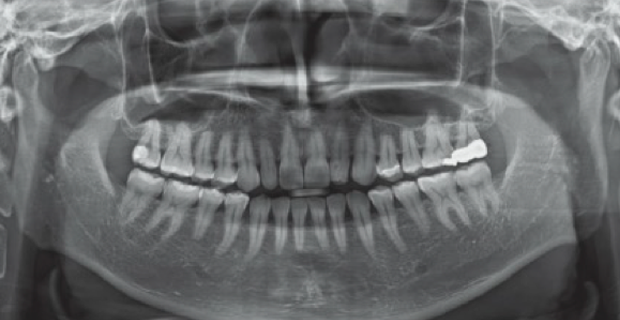

• Panoramic X-ray 촬영

낮은 방사선량으로 치아와 뿌리의 상태, 잇몸뼈의 상태,

턱관절의 형태 등을 한눈에 확인할 수 있습니다.